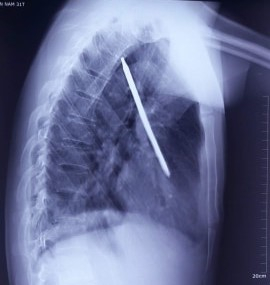

Hình ảnh chụp Xquang cho thấy chiếc tuốc nơ vít cắm sâu vào ngực nam bệnh nhân, nằm ở vị trí rất nguy hiểm.

Kết quả chụp X-quang cho thấy có dị vật kim loại dài khoảng 20 cm đâm xuyên thành ngực, nằm trọn trong phổi trái, gần tim, có nguy cơ đe dọa tính mạng bệnh nhân.